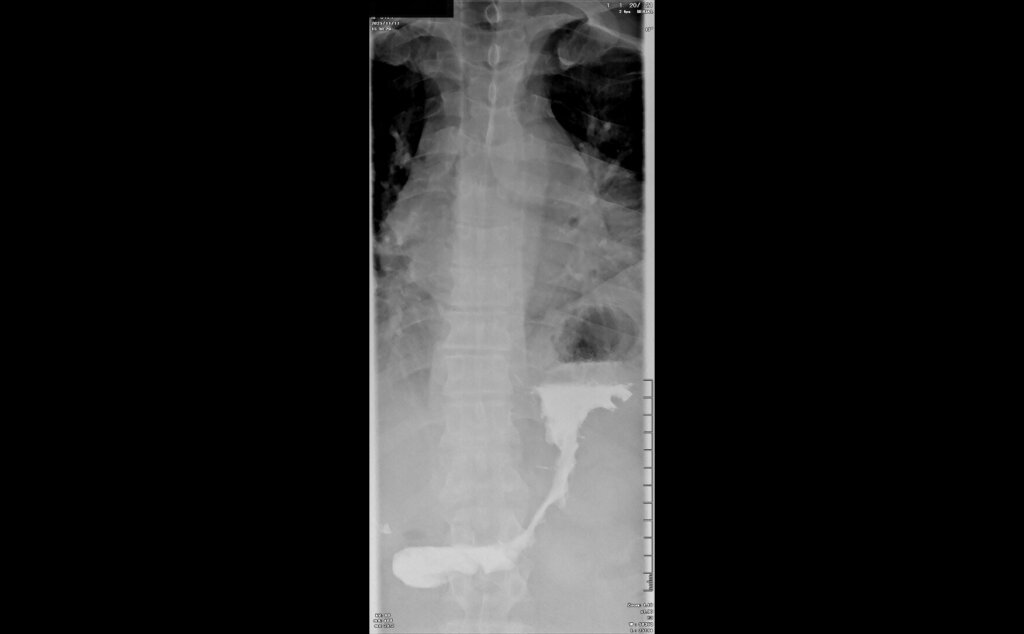

После предварительного обследования произведена операция: ESG + АПК (APC) свода; всего использовано 6 швов, время процедуры ≈ 120 минут.

Под видеоконтролем выполнена эндоскопическая рукавная гастропластика: сшивание стенок желудка при помощи аппарата Overstitch Boston Scientific по длине тела с целью уменьшения объёмов съедаемой пищи.